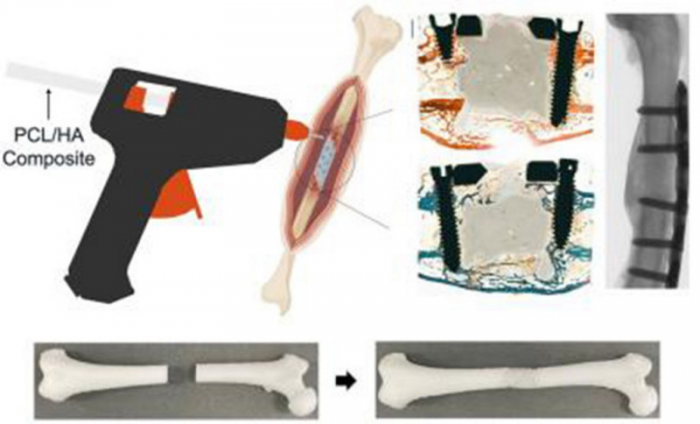

Команда биомедиков взяла стандартный клеевой пистолет и перестроила его так, чтобы он выдавливал не расплавленный пластик, а специальный кальциевый состав. Этот материал ведет себя как живая кость, поэтому его можно наносить прямо на перелом во время операции, послойно выстраивая недостающий фрагмент.

Авторы новой работы предложили другой ход: вместо изготовления готового импланта хирург получает инструмент, который печатает костный заменитель сразу в ране.

Филамент для клеевого пистолета сделали из двух основных компонентов. Первый — поликапролактон, биодеградируемый полимер, который уже применяли как основу для костных каркасов.

Второй — гидроксиапатит, минеральная форма кальция, отвечающая за жесткость и структуру костной ткани. Внутрь дополнительно ввели два антибиотика: они постепенно выходят из материала в течение нескольких недель и снижают риск инфекции, особенно опасной при сложных переломах.

Пистолет модифицировали так, чтобы он выдавливал кальциевый филамент при низкой температуре, безопасной для живых тканей. Небольшие конструкции, напечатанные этим составом, охлаждались до температуры тела примерно за сорок секунд.

Свою систему ученые проверили на новозеландских белых кроликах. Животным моделировали переломы лап, фиксировали кость пластинами и винтами, а образовавшиеся дефекты заполняли либо новым костеподобным материалом, либо привычным костным цементом.

Затем за состоянием животных и процессом заживления наблюдали в течение двенадцати недель, оценивая рост новой кости и поведение импланта. В группе, где использовали костный состав из поликапролактона и гидроксиапатита, формирование костной ткани шло активнее, а структура регенерата оказывалась плотнее, чем при классическом цементе. По итогам трех месяцев исследователи увидели более выраженное заполнение дефекта собственной костью.